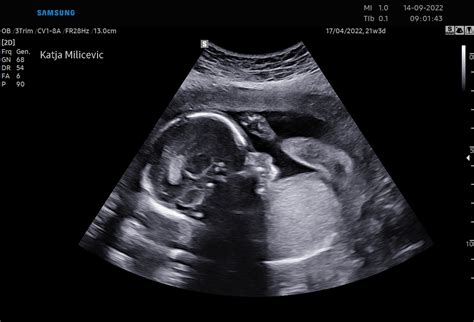

- Morfološki pregled ploda (18.-23. teden): Natančna ocena plodovih organskih sistemov za prepoznavanje morebitnih nepravilnosti v razvoju. V tem času je možno tudi določiti spol otroka.

V tem tednu je mogoča že napoved spola otroka, saj je zunanje spolovilo dobro vidno pri ultrazvočnem pregledu. Prav tako je v 17. tednu priporočljivo opraviti kardiocentezo, če je potrebna za dodatne diagnostične informacije o kromosomskih napakah ali okužbah, čeprav je to invazivna metoda.